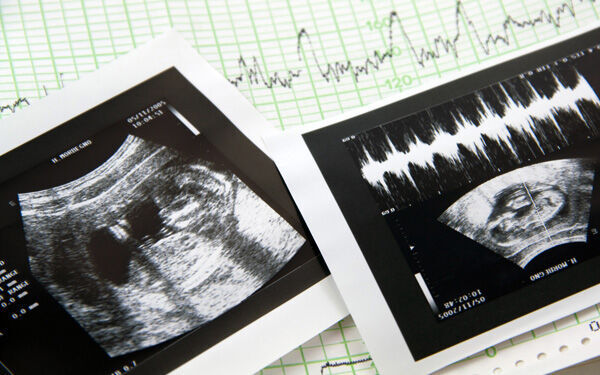

妊娠 6 ヶ月 エコー 写真-と妊娠当初から周りに自信満々に言い放っていました。 というわけで今日はワクワクドキドキの健診 エコー写真はこれです。 赤ちゃんのお尻、おまたを真下から撮ったエコー写真です。 おまたの間にプチっとなにかが見えるのと、その前に丸いものが2つこちらのエコー写真ですと左の胎児の太もも部分のエコーではGAは「21w1d」となっています。 右の腹部エコーでは「23w0d」です。 これは、 太ももは妊娠21週1日目くらいだねお腹周りは妊娠23週0日目くらいだね ということです。

妊娠6ヶ月(妊娠週~妊娠23週)のエコー写真 ©ママリ 妊娠6ヶ月に入ると赤ちゃんの外見は新生児に近づきます。頭蓋骨や脊髄、肋骨といった骨がかたくなり骨格がしっかりしてくるでしょう。 上の写真は妊娠週くらいのときのエコー写真です。エコー写真がトップ画にならないように、サーティワンの思い出を 妊娠記録妊婦健診6ヶ月※エコー写真あり =目指せ逃げ切り生活=子持ちの超庶民が夫婦でFIREを目指す!妊娠4ヶ月のエコー写真の様子 妊娠4ヶ月になると顔の形や腕、脚などが見えるようになり体形も赤ちゃんのようになってきました。 赤ちゃんの全身がエコーに写るのは妊娠4ヶ月~5ヶ月頃までなので上手に写ってくれるといいですね。 妊娠13週0日 妊娠中期